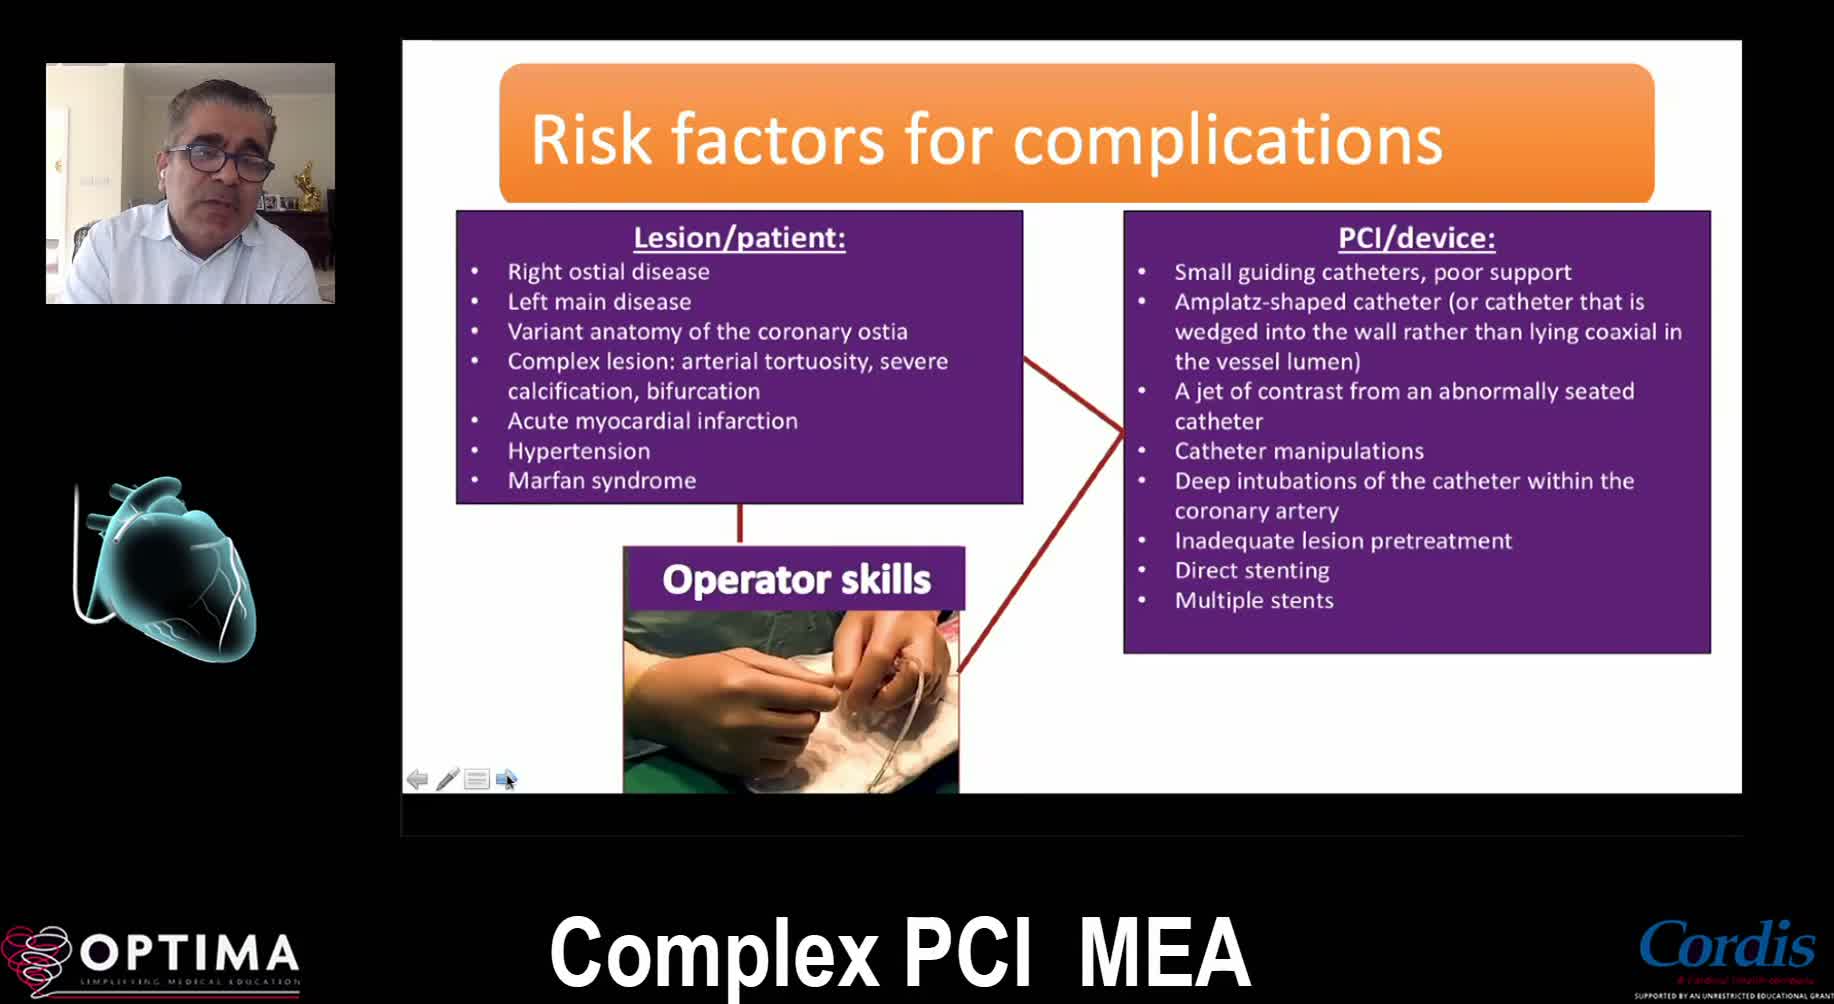

Complex PCI Middle East April 2021